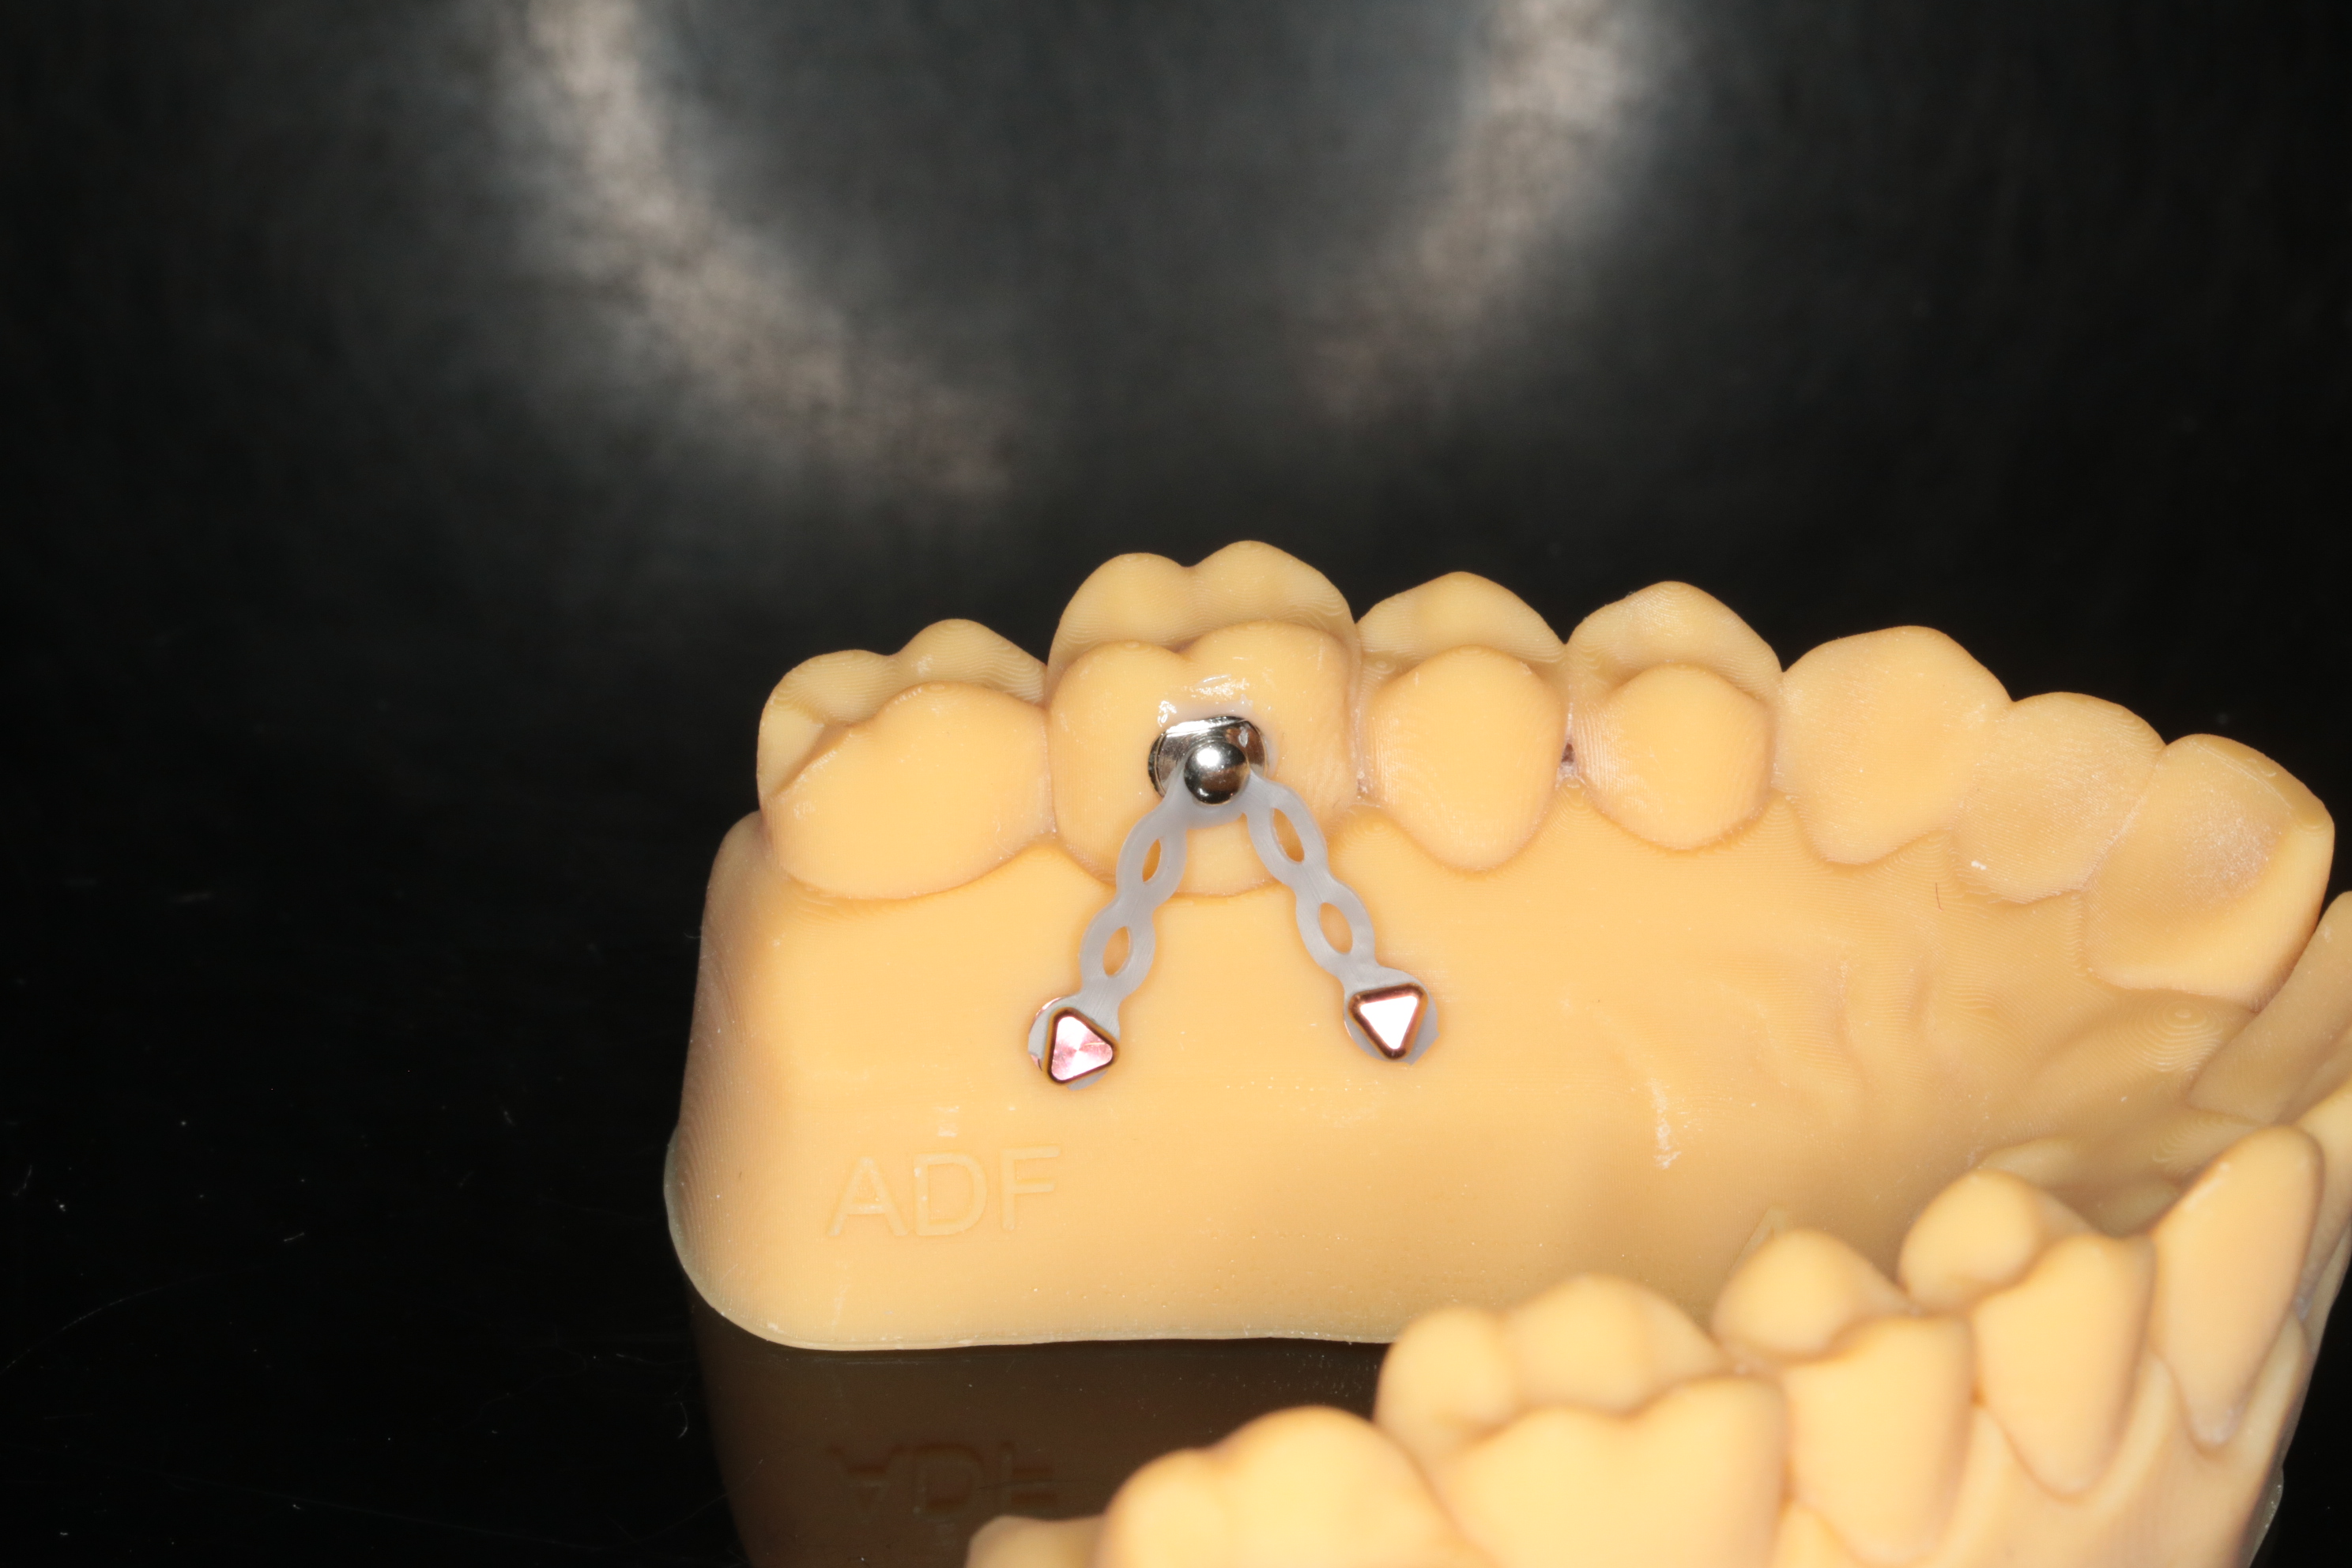

"Les mini vis"

Aix en Provence le lundi 19 janvier 2026

Lors de ce cours réalisé pour l’Académie du Sourire vous pourrez en une journée vous initier à la pose des mini-vis d’ancrage et aux notions simplifiées du déplacement dentaire unitaire.